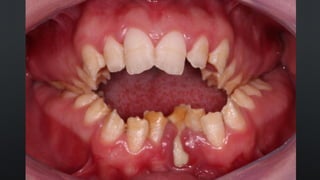

RELAÇÃO INTERDENTAL

• DISCREPÂNCIA MUSCULAR : DESLOCAMENTO DA POSIÇÃO NEUTRA

• HÁBITOS PARAFUNCIONAIS: CHUPAR DEDO, CACHIMBO, INSTRUMENTOS

MUSICAIS

• POSICIONAMENTO PROMOVIDOPELA MUSCULATURA PERIORAL DURANTE A ERUPÇÃO • ESPAÇO NO ARCO • DENTE DIRECIONADO PARA A POSIÇÃO NEUTRA • FALTA DE ESPAÇO NO ARCO • APINHAMENTO RELAÇÃO INTERDENTAL

• DISCREPÂNCIA MUSCULAR: DESLOCAMENTO DA POSIÇÃO NEUTRA RELAÇÃO INTERDENTAL

• HÁBITOS PARAFUNCIONAIS:CHUPAR DEDO, CACHIMBO, INSTRUMENTOS MUSICAIS RELAÇÃO INTERDENTAL